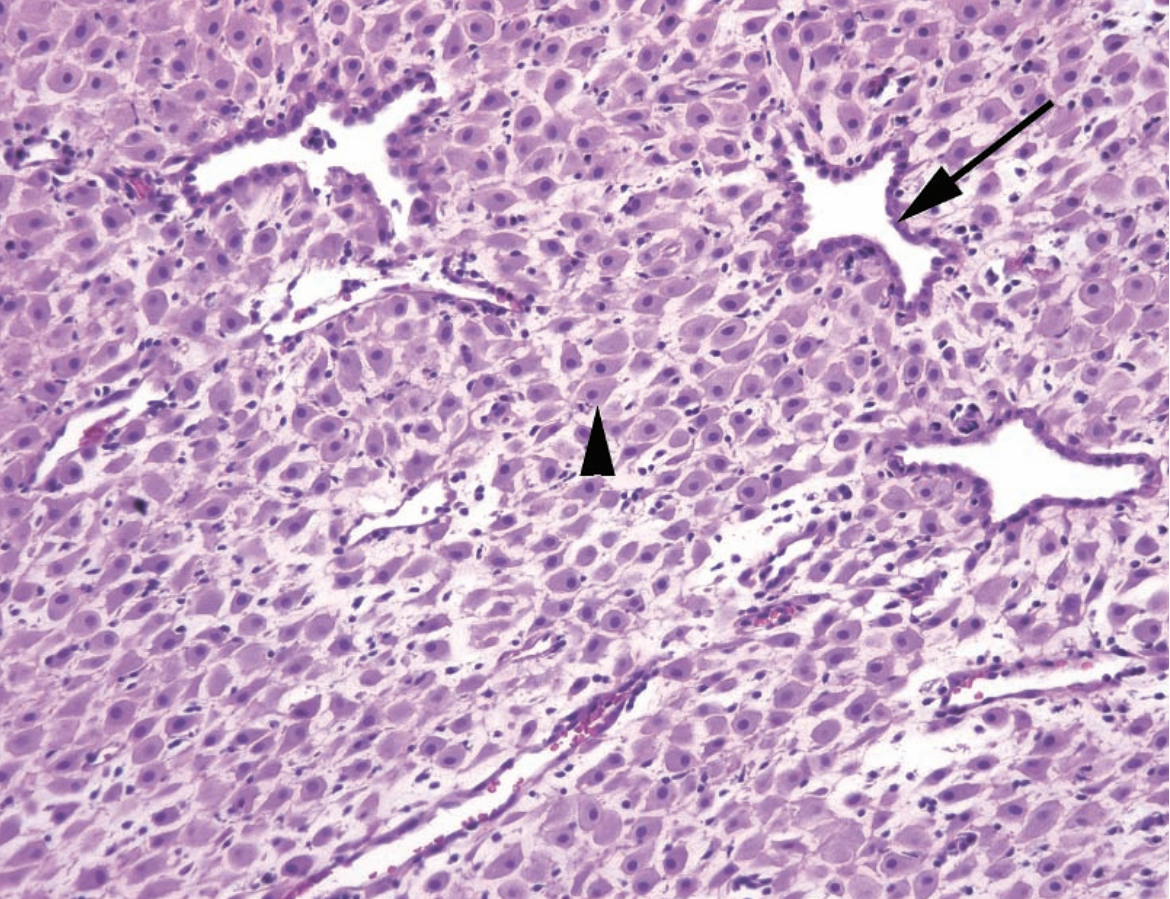

A

(late) Secretory endometrium

Arrow: Subnuclear cytoplasmic vacuoles

Arrowhead: Decidualization around the spiral arteries